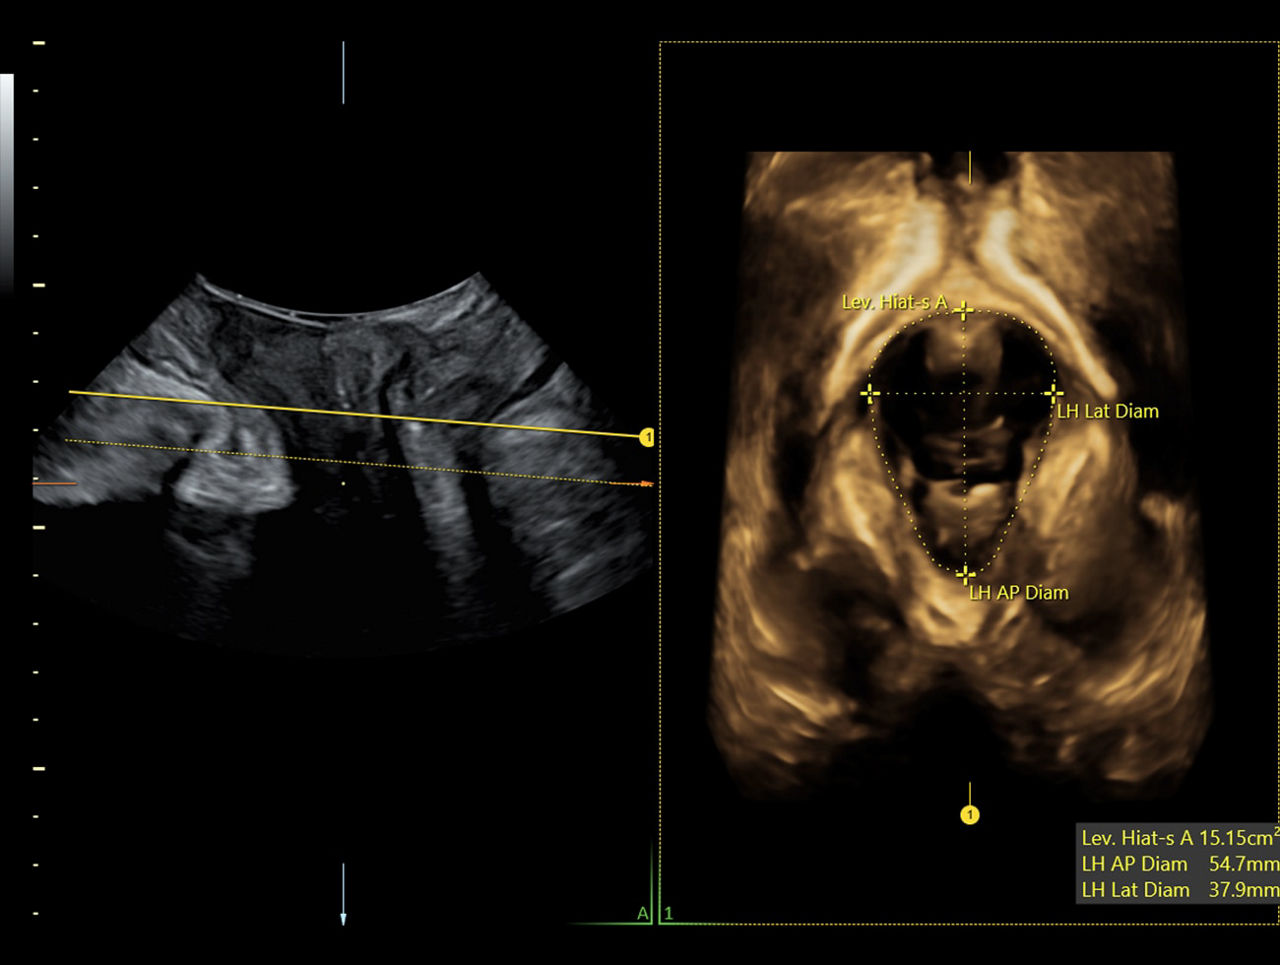

SonoPelvicFloor2.0

Guided workflows

Analysis of the pelvic floor anatomy can be complicated. Through AI, SonoPelvicFloor2.0 simplifies the exam process by automating, plane alignment, live C-plane tracking, and measurements while offering workflow guidance to improve efficiency while eliminating uncertainty.